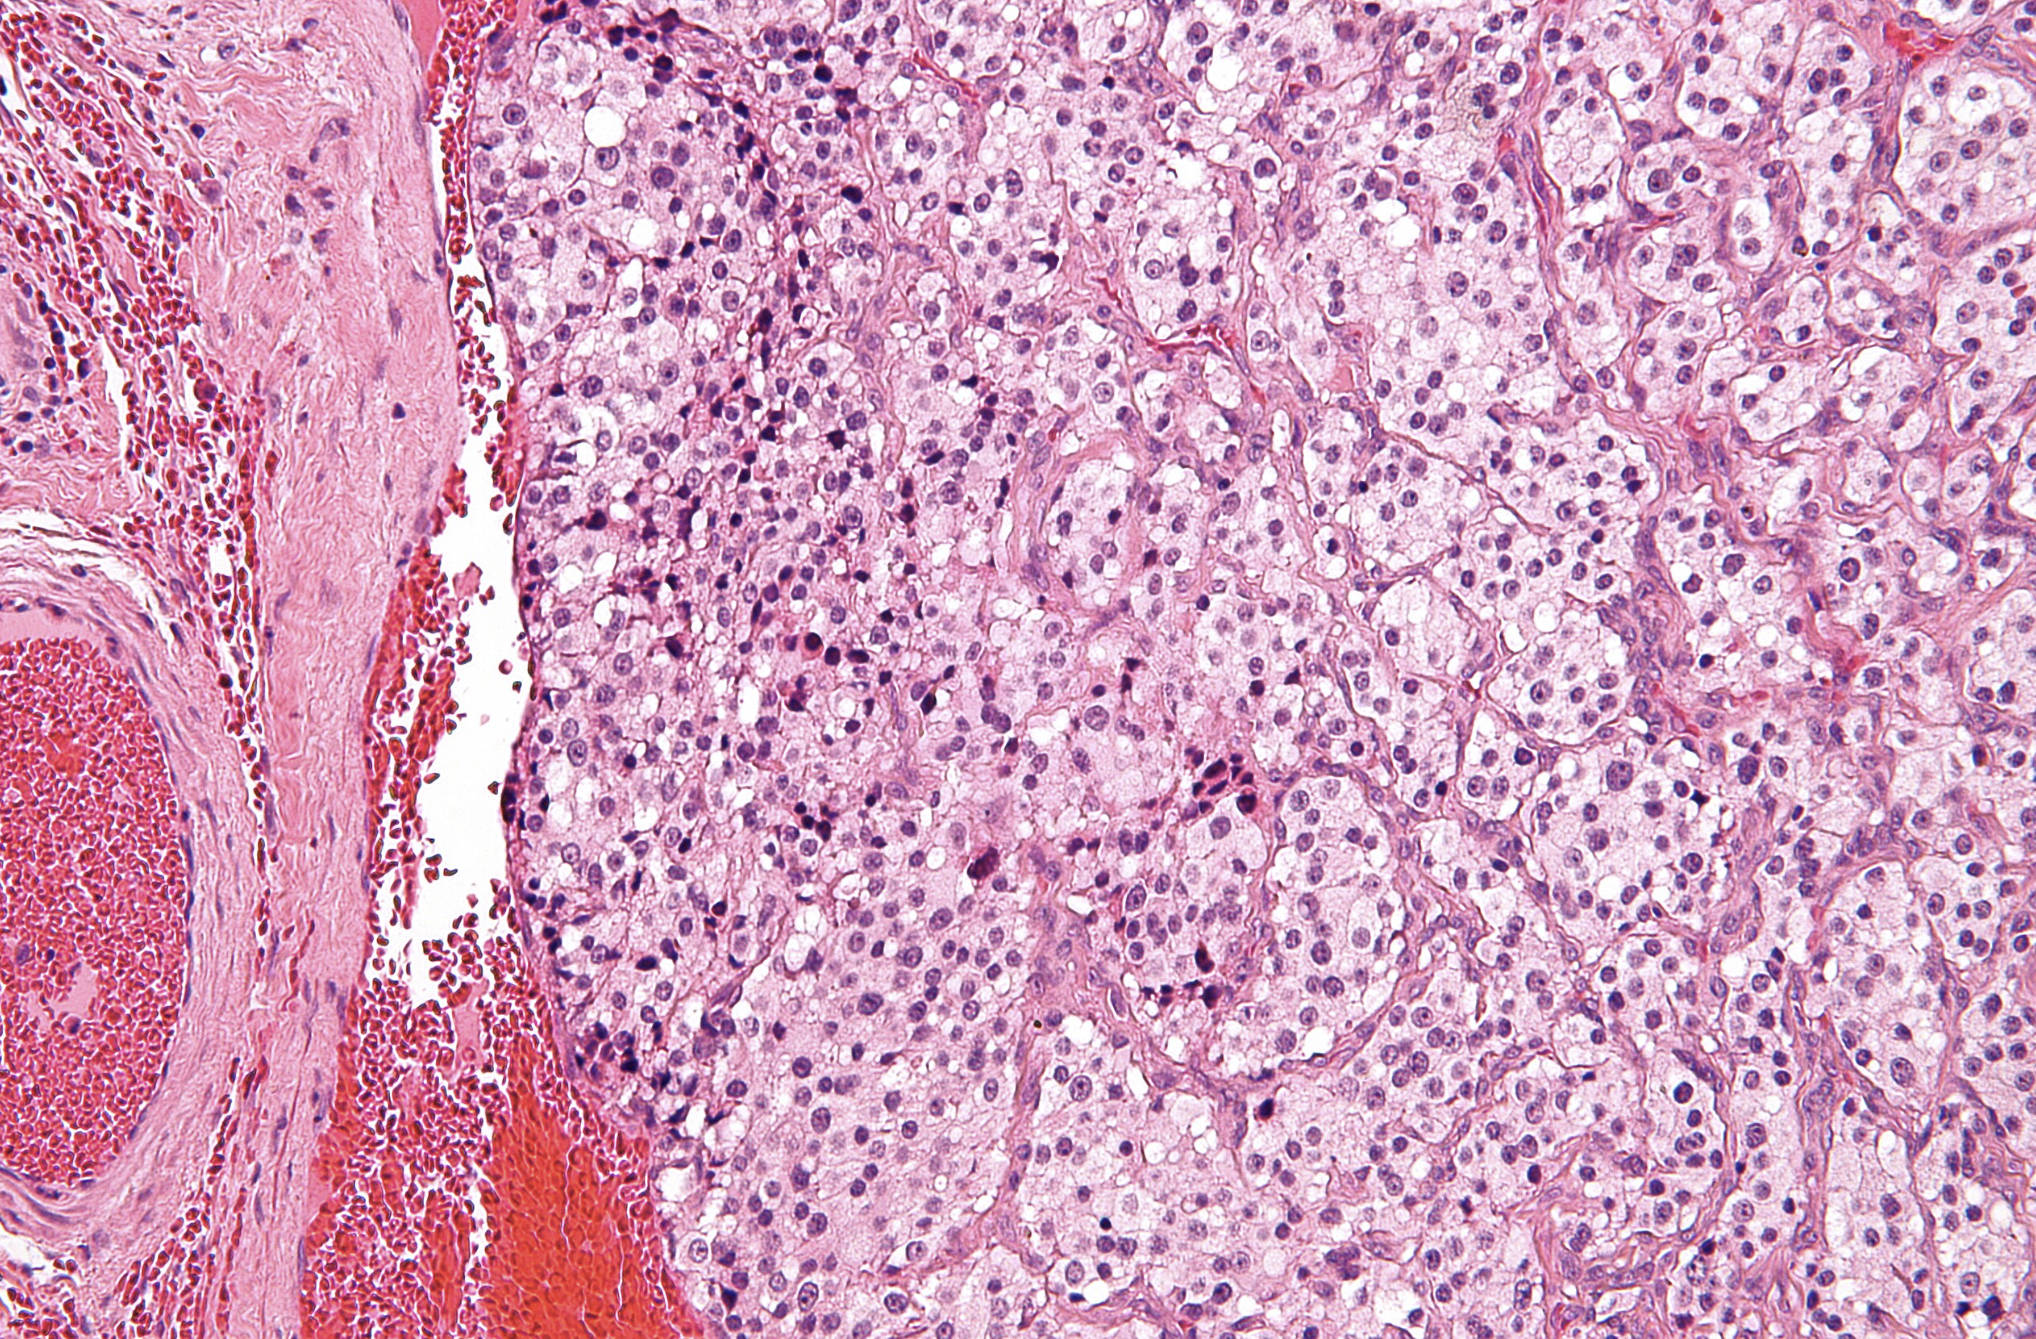

Zellballen Pattern: This term refers to the characteristic organoid or nested arrangement of cells seen throughout the tissue sample. These nests are separated by a fine, delicate fibrovascular stroma that gives the tumor its distinct mosaic appearance under the microscope.

Chief Cells: These are the predominant neoplastic cells found within the Zellballen nests, characterized by their polygonal shape and abundant granular cytoplasm. They contain neurosecretory granules that can be highlighted using specific immunohistochemical markers like synaptophysin or chromogranin.

Sustentacular Cells: These are specialized supporting cells located at the periphery of the cell nests, often appearing spindle-shaped or flattened. Although they are difficult to distinguish on standard H&E staining, they are crucial for the structural integrity of the paraganglion tissue.

Rich Vascular Stroma: The image displays an extensive network of thin-walled capillaries and blood vessels surrounding the cellular clusters. This high degree of vascularity explains why these tumors often present as pulsatile masses and carry a high risk of intraoperative bleeding.

Microscopically, the carotid body tumor is a classic example of a paraganglioma. The “Zellballen” (German for “cell balls”) pattern is the most defining feature. This pattern consists of clusters of round-to-oval chief cells surrounded by a single layer of sustentacular cells. The chief cells often display “salt-and-pepper” chromatin, which is a common feature of neuroendocrine cells where the chromatin is finely clumped. While the architecture is usually consistent, some tumors may show cellular pleomorphism or nuclear atypia; however, these features do not necessarily indicate malignancy.

Pathologists often utilize immunohistochemistry (IHC) to confirm the diagnosis. Chief cells typically express neuroendocrine markers such as Synaptophysin, Chromogranin A, and CD56. Conversely, the sustentacular cells are positive for S100 protein, which helps delineate the edges of the Zellballen nests. The differential diagnosis for a mass in this region includes cervical lymphadenopathy, schwannomas, neurofibromas, and branchial cleft cysts. The presence of the nested Zellballen pattern and the specific location at the carotid fork are the primary factors in ruling out these other conditions.